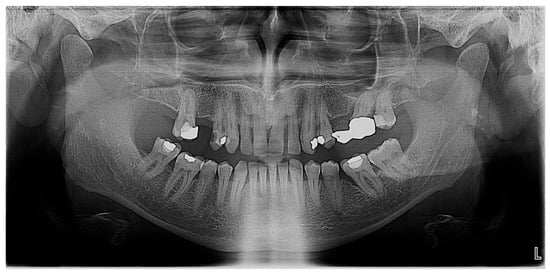

2.3. Radiologic Findings

The panoramic and intraoral radiographs revealed the internal structure of the atypical molar as well as the structure of neighboring teeth and anatomical features (Figure 4 and Figure 5). The intraoral radiographs were taken two months after the panoramic. There were no third molars in any of the quadrants. The atypical molar did not appear impacted and the surrounding cancellous bone exhibited a normal morphology, with no apparent pathologies. A mesial angular bone defect was identified in the proximal surface of the molar located distally of the second premolar, as well as a mild mesial tilting of this molar and an increased distance between its mesial root and the root of the second premolar. Horizontal bone loss was noticed between the two molars.

The atypical molar had three distinct roots, directed parallel to each other and separated by normal interradicular bone: a mesial root, a distal root and a middle root. The mesial root was the longest and the distal the shortest (as depicted in the 2D image). All roots were slightly inclined distally. The periodontal ligament space and lamina dura of the molar roots were visible and within normal limits. Two pulp chambers (the mesial and the distal) and three root canals (each root had one root canal) were visible. The mesial pulp chamber extended to the mesial and middle root canals and the distal pulp chamber to the distal root canal. The crown of the molar appeared to be divided in two unequal halves by a vertical radiopaque thin zone extending from the occlusal surface—as a continuation of the occlusal enamel, also exhibiting enamel radiopacity—to the cervical area of the middle root.

Figure 4. Panoramic radiograph of the patient.